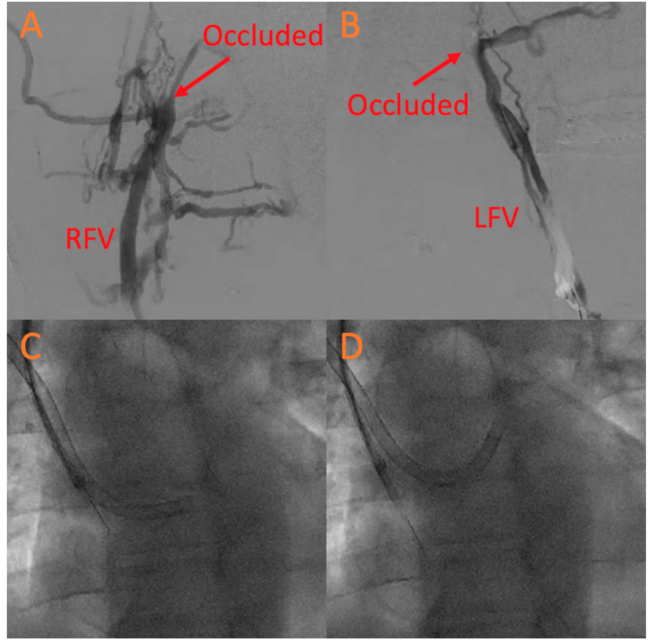

Bilateral femoral venogram was performed, confirming persistent chronic bilateral DVT (Figures 1A and 1B). Therefore, a transbrachial venous access approach was utilized. A right (12-Fr) and left (10-Fr) brachial vein access was obtained under ultrasound guidance. A 10-Fr intracardiac echocardiography (ICE) catheter (St Jude Medical) was inserted through the left brachial vein. The defect then crossed via the right brachial vein with an 8.5-Fr Agilis catheter (Abbott Cardiovascular) and exchanged for a 9-Fr 180 degree Amplatzer TorqVue sheath (St Jude Medical). However, the TorqVue sheath position was unstable in the left atrium with an unfavorable deployment angle. The intended 35-mm PFO device could fit into the Agilis sheath. Thus, a 12-Fr Oscor sheath (Oscor, Inc) was placed across the PFO (Figure 1C) under ICE guidance (Figure 1E). The Oscor sheath was then deflected upward for better alignment for PFO closure (Figure 1D). A 35-mm Amplatzer PFO occluder device (Abbott Cardiovascular) was deployed across the defect under ICE guidance (Figure 1F). Left brachial access (10 Fr) was closed with a pressure dressing, while right brachial access (12 Fr) was closed with a single Perclose device (Abbott Cardiovascular) and a pressure dressing. Postoperative transthoracic echocardiography showed stable device with no pericardial effusion.

At 1-month follow-up, the patient had perfectly healed brachial wounds (Figures 1G and 1H). To our knowledge, this is the first report on ICE-guided PFO closure via a bilateral transbrachial approach.